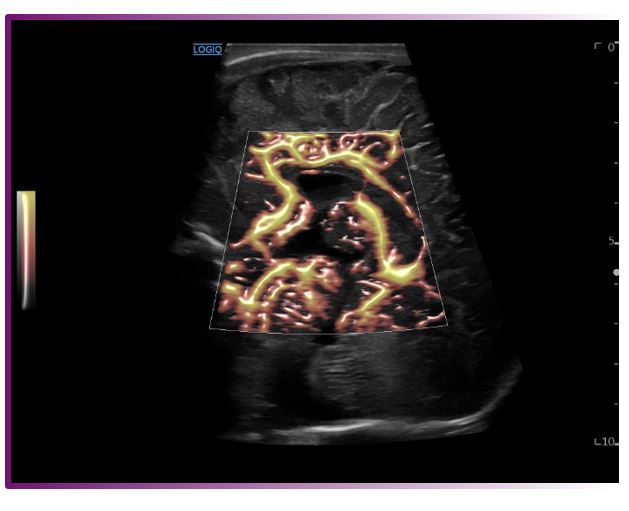

Radiant flow

포티스의 기본 옵션으로 혈류 정보를 분석해서 입체적으로 표현하는 기능입니다.

노이즈를 제거하여 미세혈관을 좀 더 선명하고 정확하게 나타냅니다.